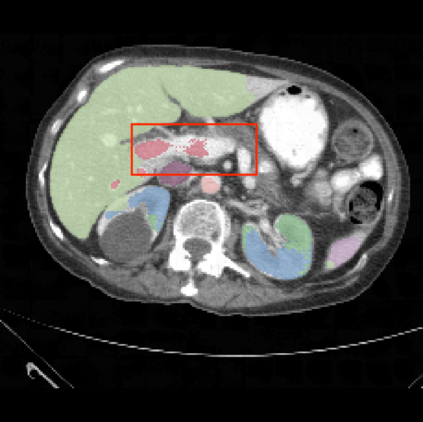

It is imperative to ensure the robustness of deep learning models in critical applications such as, healthcare. While recent advances in deep learning have improved the performance of volumetric medical image segmentation models, these models cannot be deployed for real-world applications immediately due to their vulnerability to adversarial attacks. We present a 3D frequency domain adversarial attack for volumetric medical image segmentation models and demonstrate its advantages over conventional input or voxel domain attacks. Using our proposed attack, we introduce a novel frequency domain adversarial training approach for optimizing a robust model against voxel and frequency domain attacks. Moreover, we propose frequency consistency loss to regulate our frequency domain adversarial training that achieves a better tradeoff between model's performance on clean and adversarial samples. Code is publicly available at https://github.com/asif-hanif/vafa.